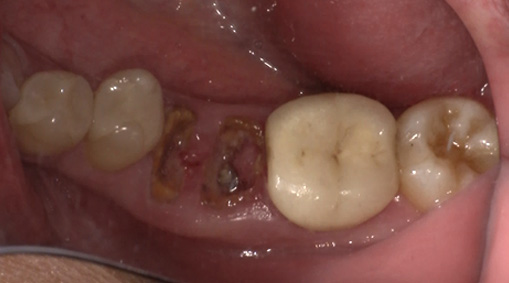

3日目:歯牙移植術を行います。

抜歯する歯の周囲に麻酔をします。

傷んだ歯を抜歯します。

親しらずを抜歯して、移植します。

歯の固定や傷口を縫合します。